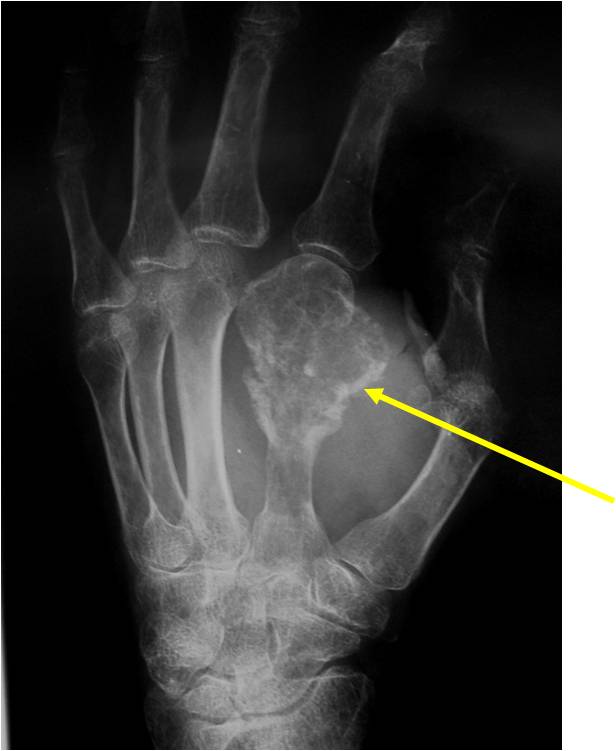

Geographic lesion, Stippled calcifications in lesion, Phalanx is expanded, Significant endosteal scalloping, No cortical destruction, No soft tissue extension, Cortex Scalloped and Expanded